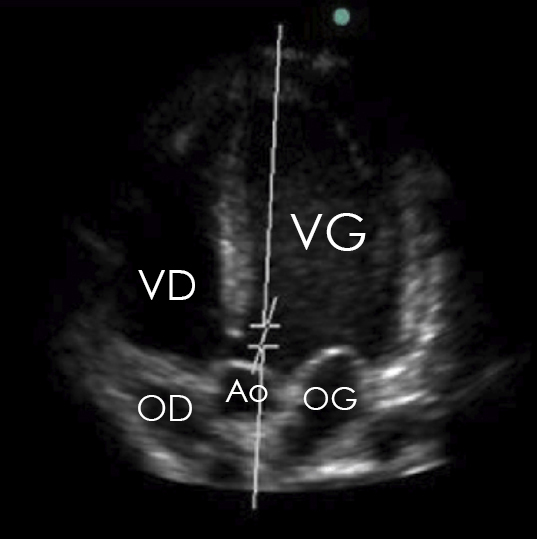

On distingue les 2 oreillettes, les 2 ventricules ainsi que l’aorte, il s’agit donc bien d’une coupe apicale 5 cavités.

On visualise la valve tricuspide entre l’oreillette droite et le ventriculaire droit, la valve mitrale entre l’oreillette gauche et le ventricule gauche, ainsi que la valve aortique dans la chambre de chasse ventriculaire gauche. La valve pulmonaire ne peut pas être visualisée sur cette coupe :

Figure 2 (Elon Zerah, La Revue du Praticien)

Il faut maîtriser les principales coupes à l’ETT pour identifier les différentes structures anatomiques intra-cardiaques : apicales 2, 3, 4 et 5 cavités, para-sternale grand axe et sous-costale.